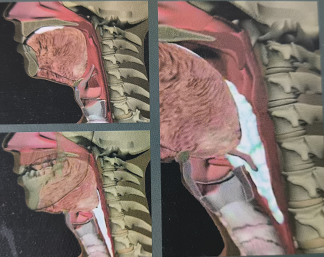

本图来源于医疗用书《吞咽障碍评估与治疗》,版权归原作者所有

吞咽障碍是由于下颌、双唇、舌、软腭、咽喉、食管等器官结构和(或)功能受损,不能安全有效地把食物送到胃内取得足够营养和水分的进食困难。

FEES为吞咽障碍诊断的“金标准”之一,通过纤维喉内镜吞咽评估可了解鼻咽部、喉部和粘膜改变,直接观察患者咽喉部的分泌物,评估咽喉部感觉,评估进食时食团运送和气道保护、声门闭合和食团清除等情况。